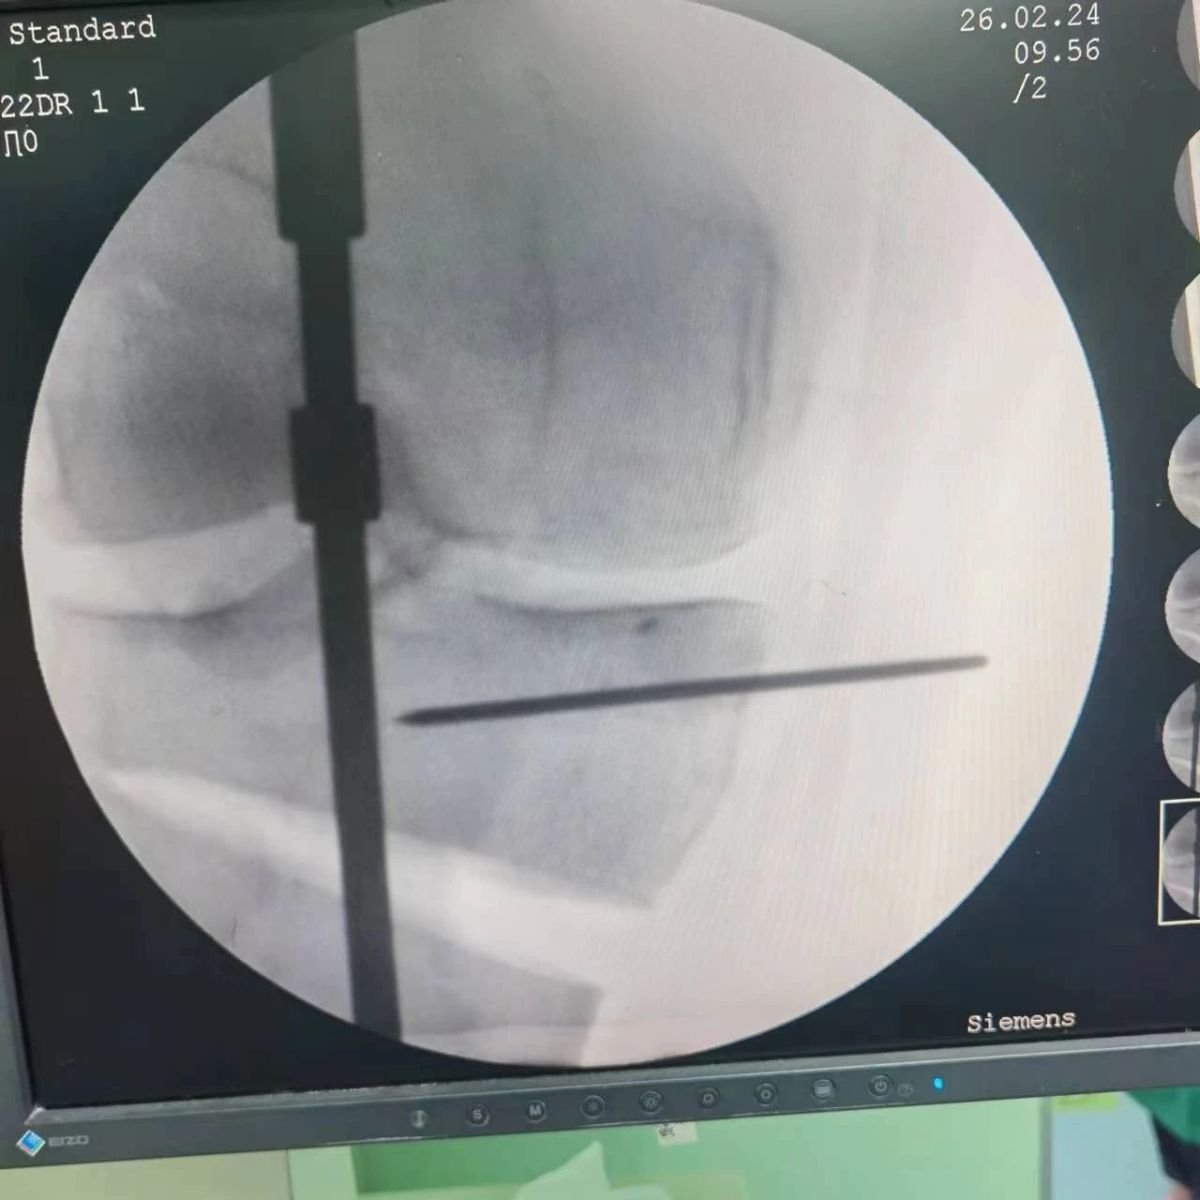

2月26日,漯河市骨科醫(yī)院(漯河醫(yī)專二附院、漯河市立醫(yī)院)膝關(guān)節(jié)外科、運(yùn)動(dòng)損傷科(骨六科)在保膝治療方面取得了新的突破,李付彬主任帶領(lǐng)岳龍等團(tuán)隊(duì)醫(yī)師,順利完成“計(jì)算機(jī)精準(zhǔn)術(shù)前規(guī)劃聯(lián)合3D打印截骨導(dǎo)板輔助脛骨高位截骨治療膝關(guān)節(jié)骨性關(guān)節(jié)炎”的手術(shù),這在漯河市尚屬首例!

患者為一名45歲男性,查體及X片可見明顯的膝內(nèi)翻,內(nèi)翻畸形主要來源于脛骨近端,關(guān)節(jié)鏡下可見內(nèi)側(cè)間室軟骨全層磨損,疼痛較重,年紀(jì)輕輕幾乎喪失工作能力。對(duì)于這種日?;顒?dòng)需求比較大的患者朋友,我們盡最大可能給予保膝治療,李付彬主任給患者詳細(xì)講解了保膝治療的方案(脛骨近端高位截骨)及預(yù)期效果,給患者帶來了極大希望。為了更精確、更微創(chuàng)的治療,李付彬主任團(tuán)隊(duì)緊跟國內(nèi)外科技前沿,采用計(jì)算機(jī)精準(zhǔn)術(shù)前規(guī)劃,并設(shè)計(jì)3D打印截骨導(dǎo)板,力求給患者帶來更精準(zhǔn)、更安全的手術(shù)效果。

李付彬主任團(tuán)隊(duì)通過精準(zhǔn)術(shù)前規(guī)劃,設(shè)計(jì)目標(biāo)力線及調(diào)整撐開角度,轉(zhuǎn)化成需要撐開的高度,最終設(shè)計(jì)出同等高度的填充塊,術(shù)中驗(yàn)證力線調(diào)整與術(shù)前規(guī)劃完全一致!

鋼板位置、螺釘位置及長度均可通過術(shù)前規(guī)劃計(jì)算,術(shù)中通過定位操作,基本與術(shù)前規(guī)劃一致,手術(shù)快速高效完成,外側(cè)合頁保留完整。無任何并發(fā)癥出現(xiàn)。術(shù)后見鋼板位置及力線糾正近乎完美!

OWHTO手術(shù)效果依賴于多個(gè)數(shù)據(jù)參數(shù),比如:截骨的入點(diǎn)、合頁位置的選擇、截骨線的深度、截骨線的方向、撐開的距離等,依托計(jì)算機(jī)術(shù)前精準(zhǔn)規(guī)劃和3D打印導(dǎo)板可輔助醫(yī)生精準(zhǔn)控制上述參數(shù),使截骨更準(zhǔn)確,真正達(dá)到精確的力線調(diào)整,減少術(shù)中透視次數(shù),縮短手術(shù)時(shí)間并降低手術(shù)風(fēng)險(xiǎn),從而使得OWHTO得到更好的應(yīng)用,造福患者。